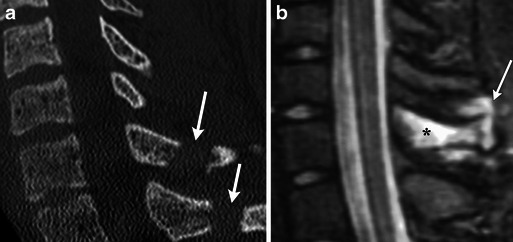

Fig. 14.

Flexion-rotational injuries: jumped and perched facets. (a) Sagittal MDCT image demonstrates anterior “jump” displacement of the inferior articular facet of C6 relative to the superior facet of C7 (white arrow). No associated fracture was present. (b) Sagittal STIR image demonstrates increased signal in the ligamentous structures between C6 and C7 (white arrow) as well as diffusely within the soft tissues (black asterisk). (c) Sagittal MDCT image demonstrates anterior displacement of C5 with “perching” on the inferior facet of C5 and the superior facet of C6 (white arrow). (d) Sagittal STIR image demonstrates cord contusion (black arrow) as well as injury to the posterior ligaments (black asterisk)